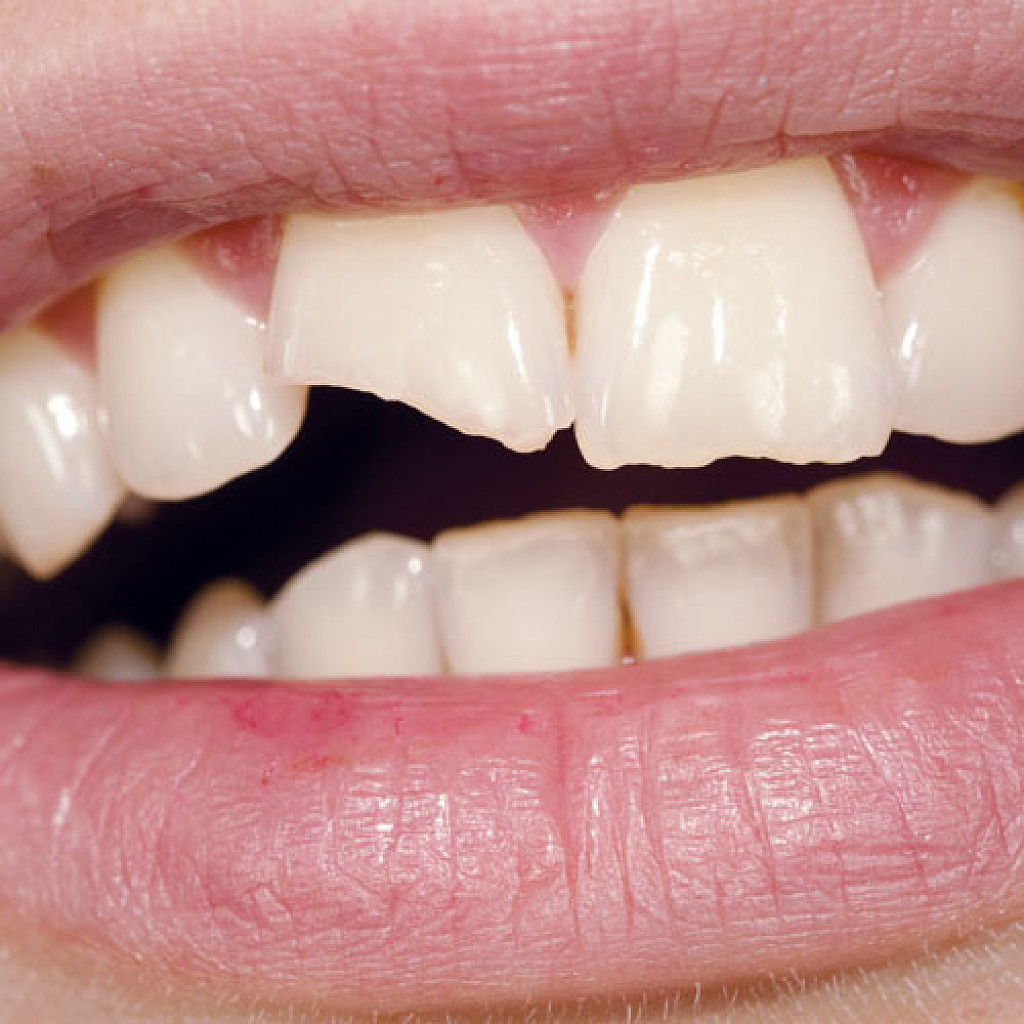

4 Longitudinal Fracture Issues And How They're Treated

Cracked teeth can happen due to a variety of circumstances: trauma due to an accident, chewing on hard food, a weak tooth structure. Sometimes, those cracks result in a type of damage called longitudinal fractures. While these fractures don’t always cause symptoms, they can cause pain and grow bacteria, which can lead to irritation and infection. Luckily, dental professionals can treat longitudinal tooth fractures, and the process to recovery will depend on the type of fracture. Here are the four types to be aware of.

Types of Longitudinal Fractures

1. Craze lines: While craze lines are considered a fracture, they’re not considered a dental emergency and generally do not need treatment. That’s because these lines only affect the tooth enamel and do not cause pain. Teeth grinding, nail-biting, or changing temperatures in the mouth may cause these types of fractures. While these cracks should not cause concern, some adults seek out cosmetic fixes like teeth whitening.

2. Fractured Cusp: Fractured cusps occur when a piece of a tooth’s chewing surface breaks off, typically near a filling. This type of fracture usually does affect your pulp or cause pain and typically can be repaired through a filling or crown.

3. Cracked Tooth: A cracked tooth is when a crack extends from the crown of the tooth toward the root, though the tooth is not split into pieces. This fracture is more extensive than a fractured cusp and, therefore, more likely to affect the nerve of the tooth. There are several possible causes for a cracked tooth, including:

4. Split Tooth: A split tooth is a complete fracture from the crown that extends below the gumline through the middle of the tooth. This is usually the result of an untreated cracked tooth, as the fracture extends over time, it can happen either suddenly or due to the long-term growth of the crack. The tooth may require extraction, but in some cases, an endodontist may save a portion of the tooth and complete a restoration to make the tooth functional.